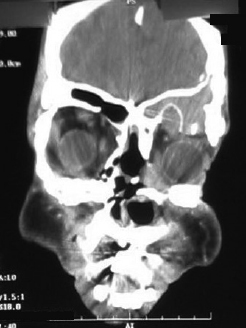

CHAPTER Traumatic injuries to the craniofacial complex can be devastating. Long-term sequelae lead to disfigurement and dysfunction if not managed appropriately. Trauma to the face can involve soft tissue, bone, salivary glands, or sensory organs. Initial management of facial trauma follows Advanced Trauma and Life Support guidelines. Once stabilized, facial injuries are treated. To optimize outcome, a systematic approach should be undertaken: 1. Accurate diagnosis by physical examination and supporting radiographic studies 2. Formulation of optimal surgical timing as well as methodology of surgical repair 3. Proper execution of treatment plan, including: • Adequate surgical exposure while following basic aesthetic principles • Anatomic reduction • Stable fixation • Optimal soft tissue management and resuspension 4. Early mobilization and proper rehabilitation Despite best efforts, treatment results of facial trauma may be suboptimal. Reduction may collapse over time because of cicatricial or muscular forces. Bony malunion or nonunion may occur. There may be poor scar formation or neurologic injury secondary to operative treatment. Unfavorable outcomes should be approached in a similar fashion to the initial injury. A methodical approach that begins with a physical examination supported by radiologic studies followed by goal-directed surgery leads to success. H.K. Kawamoto (personal communication, 2016) reiterates, “You have to know what the problem is before you can fix it.” This chapter discusses the treatment for unfavorable results of upper and midface fractures. Although rare in the facial area, infection is the first complication surgeons must watch for postoperatively. The time course may be in the initial days after the operation, but infection may not present until weeks or months later, in the form of hardware infection and exposure. If signs of infection are noted in the acute phase of healing, then simply releasing sutures or staples and gently reopening portions of the wound can be beneficial. This allows egress of infected material and exposes the wound to oxygen, inhibiting anaerobic bacterial growth. Many practitioners choose to treat perioperatively with a 5- to 7-day course of oral antibiotics that covers oral flora. For an infection that is more physiologically severe or when clinical evidence of an infection progressing beyond a localized wound is present, hospital admission is indicated. Treatment includes volume resuscitation, parenteral antibiotics, and débridement of infected tissues. Hardware infections present either in the early or late stage as exposure or purulence around plates and screws. Hardware exposure can often be treated conservatively until bony healing is complete. If bony union is not achieved, the hardware pockets are irrigated of frank purulence and débrided conservatively. The wounds can then be reclosed over a drain and a course of antibiotics given. After bony union is achieved, the hardware can then be removed. Osteomyelitis is uncommon in facial bones but can occur after excessive periosteal stripping and contamination of a fracture. Osteomyelitis presents with localized (rubor, calor, dolor) or systemic (fever, myalgias) infection. Osteomyelitis is diagnosed by a combination of bone biopsy and specific radiographic findings.1,2 Management of osteomyelitis includes surgical débridement of affected bone, removal of all internal hardware, maintaining bone orientation, and 6 weeks of intravenous antibiotics.3,4 The remaining bone segments’ orientation may be maintained by external fixation devices or replacement of plates. If the surgeon chooses to replace the internal plates, then load-bearing reconstruction plates are preferred with locking screws placed away from the site of infection in well-vascularized, healthy bone. Summary Box Unfavorable Results and Complications in the Treatment of Facial Trauma • General • Frontal sinus fractures • Naso-orbitoethmoid fractures • Orbital fractures • Zygomaticomaxillary complex fractures • Nasal bone fractures • Le Fort fractures • Panfacial fractures Scar formation from traumatic soft tissue injuries affects the result as much as bony reduction. Often, cicatricial formation of the face leads to aesthetic and functional impediments. Lacerations with crushed edges, avulsed hypoperfused superficial tissue, increased bacterial burden and local inflammation, and tight wound closure all combine to increase scar formation. To optimize cutaneous wound healing, patients should be advised to avoid sun exposure and perform scar massage or topical treatments. Massage mechanically softens the scar tissue and counteracts cicatricial thickening and contraction. Silicone gel or sheets improve scar contour and thickness.5,6 These interventions can be started after the removal of suture, provided the wound is healing well, typically after 10 to 14 days. Hypertrophic scarring appears at 3 to 4 weeks and can potentially be inhibited by serial intralesional steroid injection.7,8 This intervention will act locally to inhibit scar tissue formation. Immunomodulators such as 5-fluorouracil have also been shown in some studies to be effective.8–10 Laser and phototherapy may decrease the prominent redness of scars.11,12 If an unaesthetic scar persists beyond 6 to 8 weeks despite optimal scar therapy, scar revision and excision may be performed. This may be performed as a simple excision or other forms of local tissue rearrangement. The timing for revisions generally allows 3 to 6 months of healing to permit full resolution of tissue inflammation. As is the case with any elective procedure, it is important to medically optimize the patient for wound healing. The patient should be nutritionally optimized, tobacco free, and under adequate glycemic control. Full scar excision removes chronic inflammation and allows closure with noninflamed tissue. The wound should be designed in a way to hide it within the resting tension lines of the face, as well as to allow local tissue recruitment and tension-free closure. Abnormal fracture healing results in delayed union, nonunion, or malunion. Delayed union is slow or delayed bone healing. This occurs in cases with prolonged tissue inflammation, infection, or insufficient bone stabilization. Insufficient stabilization may be caused by screw loosening, fractures of the bone adjacent to hardware, or plate fracture. Delayed union becomes nonunion when bone fails to ossify after adequate healing time.13 A nonossified fibrous bridge often forms between bone ends and is mechanically insufficient to support the fractured segments, resulting in structural collapse against adjacent muscular or cicatricial forces. Nonunion is more likely to occur in the mandible than in the maxilla, where the forces supported are greater. Malunion is nonanatomic postreduction alignment of proximal and distal bone.14 Malunion follows poor reduction as well as hardware loosening and failure. Malunion presents with clinical findings of a step deformity at fracture segments, malocclusion, or an asymmetrical facial contour. The evaluation of malunion or delayed nonunion starts with a physical examination. It is appreciated by facial bone mobility, step-off, and asymmetry. The physical examination is followed by radiographic imaging. Computed tomography (CT) provides a thorough evaluation for bony gaps and nonviable bone. If vascularized bone flaps are necessary, CT angiography can confirm donor vascular anatomy of the flap. In these cases, the patient should be fully evaluated for physiologic tolerance for prolonged surgery. The treatment for bony nonunion involves removing the previously placed hardware and excising the fibrous bridge. Bone, as free or vascularized graft, is then used to bridge the segment, and the entire construct is supported by hardware. The length of the bone gap is important because it determines the treatment. Nonvascularized or allogenic cadaveric bone grafts adequately reconstruct defects up to 6 cm, whereas vascularized bone grafts, from the fibula or iliac crest, are ideal for defects larger than 6 cm.15 For a defect smaller than 6 cm in a nonirradiated patient, treatment options include cadaveric or nonvascularized autogenous bone graft. Adding a substance such as bone morphogenetic protein (BMP) to this site may improve osteoinductive potential, through direct stimulation of bone growth and induction of bone stem cells. These nonvascularized corticocancellous grafts are secured to the bone plate within this continuity defect. Bony defects larger than 6 cm require reconstruction with vascularized bone flaps. With these large bone gaps, vascularized bone provides osteogenic potential for healing and prevents the resorption seen in conventional bone grafts. Possible donor sites include the fibula, iliac crest, scapula, and radius, each with their own set of advantages and disadvantages. Flaps may be transferred as bone and soft tissue composite free tissue to correct soft tissue deficits. The frontal sinus begins to develop at age 6 years. In adults, the sinus is completely formed as air-filled spaces in the forehead on either side of the midline. With an average total volume of 14 mL, the frontal sinuses are composed of an anterior and posterior wall and can exist as two separate spaces separated by a bony midline septum or a large communicating single cavity.16 Mucosa lines the bony cavity and produces secretions that drain through nasofrontal ducts traversing the inferomedial sinus floor and to the nasal middle meatus. The anterior wall forms brow and forehead contours, whereas the posterior wall forms the limit of the anterior cranial fossa. Fractures of the frontal sinuses have many patterns and can include one or both sinuses; involve the anterior wall, posterior wall, or both walls; and may or may not extend to or cause obstruction of the frontal duct system. Initial treatment involves three considerations that determine the outcome. The anterior wall supports the aesthetic contours of the brow and forehead. The posterior wall supports the anterior cranial fossa and dura. Fractures injure the dura and form a communication between the brain and nasal cavity. The nasofrontal duct drains the sinus, and obstruction can lead to trapping of secretions and infection. Management of these fractures focus on restoring integrity of the anterior walls but also on the creation of what has been conceptually referred to as a safe sinus.17,18 This concept refers to preventing mucous trapping by removing mucosal elements of the sinus when the nasofrontal ducts are compromised or intracerebral infection is of concern. The initial treatment of frontal sinus fractures starts with prophylactic antibiotics. Antibiotic choice should cover gram-negative, gram-positive, and anaerobic bacteria, such as clindamycin. Anterior table fractures are reduced and plated into anatomic position. Injury to the nasofrontal duct is treated by sinus obliteration, removal of all mucosal elements, and closure of the nasofrontal duct. Displaced fracture of the posterior wall is treated by (1) cranialization, (2) removal of the posterior wall, (3) removal of all mucosal elements, and (4) repair of dural injuries. Reconstructive failure of these four elements may create undesirable results. Contour irregularity of the forehead and glabella result from loss of soft tissue, bone fragment resorption, or inaccurate realignment of the bones. If this occurs, it may be noticeable and become a stigmata of previous injury, sometimes causing patient distress. Evaluation starts with physical examination followed by CT. Scans can determine whether the aesthetic abnormality is related to soft tissue atrophy or underlying bony irregularity. Bony irregularity in the form of overlapping step deformity or irregular thickness can be burred or filed down. Options to improve soft tissue contour defects include soft tissue grafts like fascia, dermis, or fat. For large or bony defects, bone grafts as well as alloplastic materials such as prefabricated polyethylethylene or porous polyethylene may be used. Each of the aforementioned materials has its proponents, depending on the size and type of contour. Autogenous options are superior because of a decreased potential for infection or granulomatous reactions. Overcorrection is indicated to account for the expected fat and bone graft resorption over the first year and beyond (Fig. 48.1). Fig. 48.1 (a,b) A young patient presented after posttraumatic frontal sinus and bone repair with significant frontal and cranial bone loss. (c) Split calvarial bone was used to reconstruct the frontal bone, glabella, and forehead. (These images are provided courtesy of J.I. Garri.) Meningeal tears and injury can result in persistent cerebrospinal fluid (CSF) leak and secondary CSF space infection. This can either result from poor healing and sealing of the dural closure or unidentified dural tears. Evaluation for a chronic CSF leak is a clinical diagnosis but can be verified by beta-transferrin levels of the fluid. The clinical presentation is persistent clear nasal drainage. CT may be useful to identify the location of the dural defect. Dural defects are repaired by direct suture or using dural patches of free fascial graft or alloplastic collagen sheets.19,20 A preferred method is the use of vascularized pericranium or temporalis to cover suture lines (Fig. 48.2). When there is significant dead space and continued CSF leak, pericranium and temporalis flaps may be insufficient. These situations may be best dealt with using free tissue transfer, which can fill dead space, improve vascularity to the region, and stimulate sealing of the dura.21 Mucoceles of the frontal sinus result from sequestered secretions caused by partial or complete nasofrontal duct obstruction. They occur when there is an unrecognized nasofrontal duct obstruction or because of retained sinus mucosa after obliteration or cranialization and may occur years after the initial injury.22,23 Infected mucoceles are called mucopyoceles. Mucoceles expand from continued mucous secretion and compress and distort surrounding structures. Diagnosis is clinical, based on a history of frontal sinus fracture, fevers, visual symptoms, and headaches. CT defines the patient’s anatomy and structural distortion caused by the mucocele (Fig. 48.3). Early treatment of mucoceles involves ample drainage, which can be performed endoscopically if identified before significant anatomic distortion. If endoscopic drainage fails or is not technically feasible, a craniotomy is required to remove all retained sinus mucosa. Through a coronal incision, a craniotomy allows access to the mucocele. The brain is separated from the mucocele, and any inflammatory tissues are removed. The posterior table segments are removed and any remaining sinus surfaces are burred to remove all mucosal rests. Distorted facial and cranial structures are reconstructed with autologous bone graft (Fig. 48.4). The dead space is then obliterated by a pericranial or temporalis flap.23 If these are too scarred for use or have been used already, or the dead space is large, the surgeon must consider alternate options such as free tissue to close off those spaces. Fig. 48.2 A collagen alloplastic patch is used to seal the dura. (This image is provided courtesy of J.I. Garri.) Fig. 48.3 After a frontal sinus fracture, this patient presented with a left-sided mucopyocele that destroyed the orbital roof and rim. (This image is provided courtesy of J.I. Garri.) Fig. 48.4 (a) After a frontal sinus fracture with mucopyocele formation, this patient’s anterior table had irregularity and openings into the sinus. (b) Resection of necrotic bone exposed the sinus and allowed débridement of the mucopyocele and separation from the brain. (c) Reconstruction is with split calvarial bone graft. (These images are provided courtesy of J.I. Garri.) The naso-orbitoethmoid (NOE) region is a complex focus of bony articulations involving multiple facial buttresses. Here the nasal bones and cartilages, maxillary frontal processes, lacrimal bones, orbital plate, ethmoid air cells, cribriform plate, and frontal bone adjoin. NOE fractures affect the shape and position of the nasal pyramid, root of nose, and medial canthus. Accurate reduction prevents contour and symmetry irregularity of the nasal sidewall. The grade of injury determines the surgical maneuvers necessary to correct the medial canthal deformities. This includes reduction or fixation of fractured segments and transnasal wiring. Telecanthus is an increased distance between the medial canthi.24 It is a soft tissue relationship and differs from hypertelorism, which is increased interpupillary distance.25 The normal intercanthal distance equals the length of the patient’s palpebral fissure, approximately 31 to 33 mm.26 This is a gender-specific and ethnically variable measurement. Malpositioned medial canthi is a challenging problem to correct. Poor medial canthal position and appearance can be caused by soft tissue secondary healing and bone malposition. The evaluation should include a keen physical examination correlated with CT to better define the bone and soft tissue relationship. Scarring and fibrosis of the soft tissue around the medial canthal tendon distorts its position, leading to degrees of telecanthus. Alternatively, the previous medial canthal wiring may erode the bone and allow the canthus to slip laterally. This situation is most easily addressed with tissue rearrangement using small, local flaps. Horizontal discrepancies can be corrected with V-Y advancement, whereas vertical discrepancies are addressed with z-plasty–style transposition flaps. These flaps should be full-thickness tissue down to bone. The flap controlling the canthal angle is then reanchored to bone by a transnasal suture or wire to maintain the new soft tissue position. The wiring traditionally is performed by coronal incision, but a transcaruncular approach is a less invasive. The wire is passed posterior and superior with slight overcorrection. Alternatively, if bone erosion is a concern, a small plate may serve as the fixation point for the transnasal wire. If the bones are malpositioned, then a bone-centric approach is required. This starts by removing previous hardware and re-creating the NOE fracture via osteotomy and correctly reducing the segments. If the medial canthal tendon (MCT) is not fixed to these segments, it may still require transnasal canthopexy to achieve the anatomic position. Of note, the technique is very difficult, and the best secondary treatment of telecanthus is not defined. Skin thickness and tissue draping of the canthal–sidewall junction can be worsened by edema and is a stigmata of the injury. Transnasally fixed bolster dressings on both canthal–sidewall junctions help control the edema and maintain the soft tissue. These should be left in place for 7 to 10 days. Lacrimal apparatus damage occurs either from the injury or during the initial repair. The normal course of tears flows from the upper and lower puncta, through the superior and inferior canaliculi traversing the orbicularis, into the lacrimal sac in the lacrimal fossa, and through the lacrimal duct, exiting under the inferior nasal turbinate. Considering that 90% of tear volume evaporates, injuries may never be identified. Approximately 17% of nasolacrimal duct injuries associated with NOE fractures require surgical correction.27 Evaluation starts with determining a history of excessive tearing postoperatively. Traumatic telecanthus may be part of the history, because it is associated with lacrimal duct obstruction.28 Postoperative eyelid malposition should also be considered, because eyelid incisions are commonly used in facial open reduction and internal fixation. Epiphora may be expected in the initial postoperative period from edema of the lacrimal apparatus, but persistence beyond the normal healing time of 6 weeks necessitates testing. CT imaging can help identify bony fractures involving or occluding the lacrimal duct. Jones (primary dye test) test confirms lacrimal duct obstruction, with a sensitivity of 97% and specificity near 100%.29 Jones test 1 is performed, in which fluorescein is instilled at the medial canthus and subsequently drained at the inferior turbinate onto a cotton applicator. A positive test shows the duct is patent. If the test is negative, Jones test 2 is performed, which involves cannulation of the lacrimal duct and injection of fluorescein under pressure. A positive test means partial obstruction or stenosis of the lacrimal apparatus exists. Dacryocystorhinostomy is the operative repair of nasolacrimal dysfunction. This procedure is performed classically through an external open technique or endoscopic transnasal approach. External dacryocystorhinostomy begins with a well-placed incision within the medial orbital soft tissue, medial to the MCT. Dissection is carried down to the periosteum over the lacrimal crest. Periosteum is cleared from bone anterior to the lacrimal fossa, and the lacrimal sac is identified by passing a probe through the puncta. An osteotomy is made anterior to the lacrimal fossa to expose the nasal mucosa with a high-speed bur. The nasal mucosa is then elevated from bone and incised. A mirrored incision is made into the lacrimal sac. Crawford tubes are passed through superior and inferior canaliculi into the lacrimal sac. The terminal ends of the Crawford tubes are then placed through the osteotomy into the nasal cavity. The tubes are trimmed to stay within the nasal vestibule and secured with suture. An ostomy between nasal and lacrimal sac mucosa is then created by suturing the open mucosal edges. The skin incision is closed in layers, emphasizing aesthetics. Crawford tubes remain in place for at least 3 weeks to up to 6 months to maintain patency of the surgically created nasolacrimal fistula. A significant posttraumatic deformity caused by NOE fractures is the loss of nasal projection. The contours of the nose are supported by the nasal process of the frontal bone, the nasal bones, the frontal process of the maxilla, the septum, and upper and lower lateral cartilages. Significant trauma to the NOE complex may result in depression of its subunits and loss of support for the nasal pyramid. This may lead to upper and middle nasal vault deficiency, concavity of the nasal dorsum, and loss of nasal length or tip projection. Further secondary nasal reconstruction is discussed in the Nasal Bone Fractures section. With facial trauma, the bony support may be significantly distorted, such as in NOE fractures, and overlying soft tissue may heal in an unaesthetic manner. The surgeon should be careful when closing the soft tissue envelope at the initial repair, because wound dehiscence and widened scars may complicate healing. The medial orbit and canthus is an area of concern when underlying skeletal contours are altered and soft tissue swelling results. Prolonged tissue edema causes tissue thickening and loss of fine soft tissue anatomy. This may result in epicanthal folds, blunting of the medial canthal angle, or disruption of the canthal tendon repair. This is best treated with prevention. A rigid bolster dressing is placed on both nasal sidewalls and secured transnasally with suture. A rigid dressing can be assembled using a halved aluminum foam nasal splint or rolled petroleum gauze. Secondary revision can be quite complex and rarely will restore premorbid aesthetics. The soft tissue is rearranged as outlined in the Telecanthus section. Forces transmitted hydrostatically through the globe or through adjacent bones fracture the orbital walls.30 They are also associated with high-level midface fractures like Le Fort II and III patterns. Although blow-in fractures occur, blowout fractures are more common and result in increased orbital volume, restricted extraocular movement, and visual disturbances. The globe is evaluated for injury before repair to prevent exacerbation of injury and blindness. At primary repair the goals of treatment are restoration of correct orbital volume and reduction of orbital rim step-offs. This is performed through transconjunctival, subciliary, and subtarsal incisions. The orbital wall defects are closed with either autogenous bone graft, resorbable and nonresorbable synthetic plates, or titanium plates. Orbital floor reconstruction plates are positioned on the posterior ledge of the fracture to accurately re-create volume. Poor outcomes from orbital fractures include ocular injury, diplopia, enophthalmos, eyelid malposition, and hardware complications. Ocular injury after orbital fractures is common, occurring in approximately 60% of cases.31 The incidence increases as the number of other associated facial fractures increases. Associated ocular injuries include hyphema, retinal injury and hemorrhage, ocular hypertension, optic neuropathy, and globe rupture.31 Delayed repair of the orbital fractures is necessary to allow these injuries to stabilize. Any of these preexisting injuries can progress to blindness if not managed appropriately and with caution. Ocular injury may also occur during the dissection of the orbital defects by blunt force. The optic nerve enters the superomedial orbit approximately 40 mm from the orbital rim. Iatrogenic complications are rare and are best treated with prevention. A rare complication after injury is sympathetic ophthalmia. This condition typically follows globe rupture. The clinical presentation results from a coordinated feedback response loop between injured excitatory and the uninjured sympathizing eyes. The injured eye presents with decreased vision stimulating photophobia, visual accommodation paresis, and pain in the sympathizing eye. The mainstay of treatment is enucleation within 2 weeks of injury upon failed improvement of vision. Medical treatments include high-dose steroids, immune modulators such as cyclosporine and mycophenolate, or intraocular injection of steroids.32 Diplopia results from the initial trauma or after surgical intervention. It is important to document diplopia and how it presents at rest or extremes of gaze. After orbital surgery, continued diplopia occurs in 8 to 30% of patients.33 Diplopia incidence increases in older patients after delayed orbital fracture repair.34 Immediate postoperative swelling of extraocular muscles may contribute to diplopia; following an interval for edema resolution, continued diplopia requires further workup. A thorough history and physical examination is performed, with ophthalmologic consultation, to diagnose the cause. Diplopia immediately after the initial reconstruction may be caused by plate impingement on extraocular muscles. Causes of persistent postoperative diplopia include intraocular pathology, extraocular muscle dysfunction, and discrepancies in globe position from enophthalmos or hypoglobus. CT will further define the extraocular anatomy and areas needing orbital volume correction. The treatment for diplopia depends on the cause, and subsequent correction of such typically ameliorates the visual disturbance. If diplopia persists, corrective lenses may be used to further improve symptoms. Although both conditions can occur concomitantly, enophthalmos is underprojection of the globe in the anteroposterior plane, whereas hypoglobus is caudad globe displacement into the space of the maxillary sinus. Both enophthalmos and hypoglobus cause extraocular muscle dysfunction by changing the axis of muscular action. Enophthalmos is quantified by two methods. A Hertel exophthalmometer directly measures the corneal lateral canthal distance. Immediately postinjury or postoperation, this measurement will be normal or exophthalmic because of periorbital swelling. Enophthalmos may not develop until several weeks after the injury. CT may be used to calculate orbital volume and approximate the difference from normal.35 Both of these conditions may cause periorbital asymmetry, cosmetic concerns, and disruption of the visual axis and can oftentimes be associated with diplopia. Postoperative enophthalmos and hypoglobus result from improper reconstruction of orbital volume, atrophy of traumatized orbital fat, or resorption of autogenous bone graft materials used in the repair. Orbital volume requires correction to resolve globe position problems. Causes include plate malposition projecting into the maxillary sinus, or poor plate adaption creating an oversized orbit. This reconstructive error must be revised by adapting the plates to correctly rest on the posterior ledge of the fracture, thus reducing orbital volume. The orbital volume can be fine-tuned with bone graft in addition to plates (Fig. 48.5).